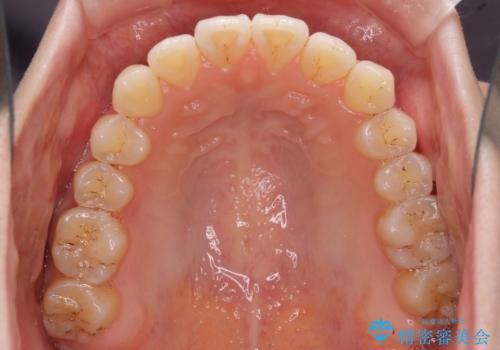

オープンバイトのインビザラインを用いた再矯正

- 矯正治療の後戻りを気にして来院された患者様です。

オープンバイト(前歯の開咬)と下顎骨の偏位による不正咬合が認められました。

骨格の偏位による不正咬合は改善しきれないことを理解いただいた上で、インビザラインにて矯正治療を行うこととしました。

オープンバイトは後戻りを起こしやすいため、極力そのリスクを軽減するため、奥歯を圧下させるように治療を進めていきました。

下顎骨の偏位が顕著であったため、上下の正中を合わせることはできませんでしたが、患者様には大変満足していただきました。